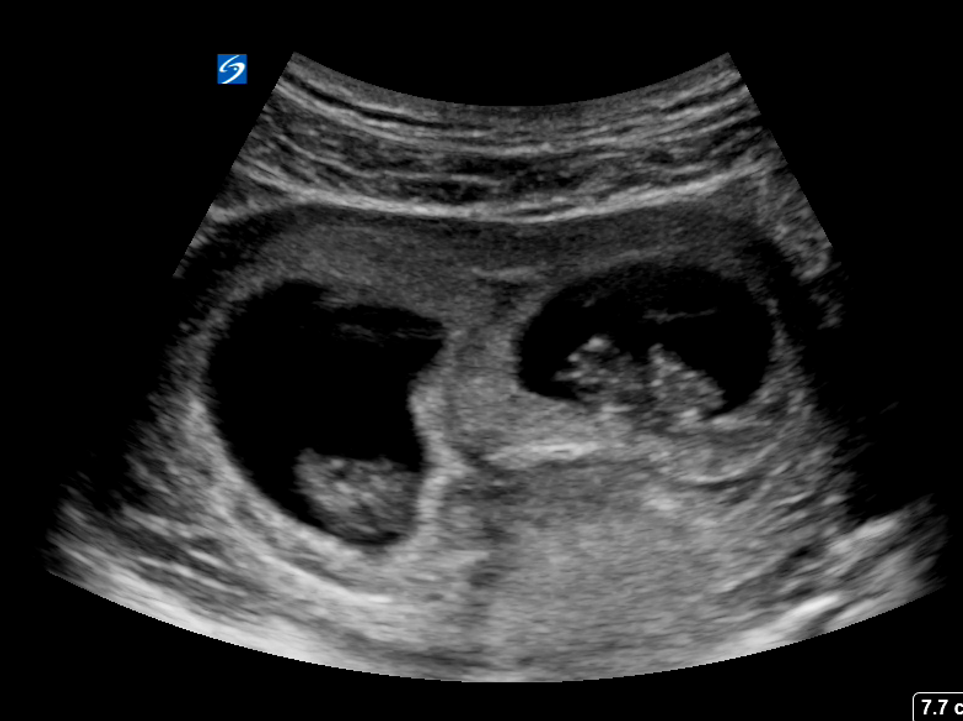

7- حدود یک در 250 بارداری منجر به دوقلوهای همسان می شود.

12. یک مطالعه جدید نشان داد که دوقلوها در اوایل بارداری 14 هفته در رحم پیوند می خورند.

در سال 2011 ، محققان Umberto Castiello از دانشگاه پادووا در ایتالیا فیلم های سه بعدی از دوقلوها را در رحم مادرشان مطالعه کردند. در 14 هفته حاملگی ، دوقلوها به یکدیگر نزدیک شدند. تا 18 هفته ، آنها بیشتر از آنکه بدن خود را لمس کنند ، یکدیگر را لمس می کردند. محققان گفتند که تجزیه و تحلیل سینماتیک ضبط ها نشان داد که این دوقلوها حرکات متمایزی نسبت به یکدیگر ایجاد کرده اند و به همان اندازه که در هنگام لمس کردن خود ، نسبت به ناحیه ظریف چشم ملایم بوده اند در مورد دیگری نیز رعایت کرده اند.